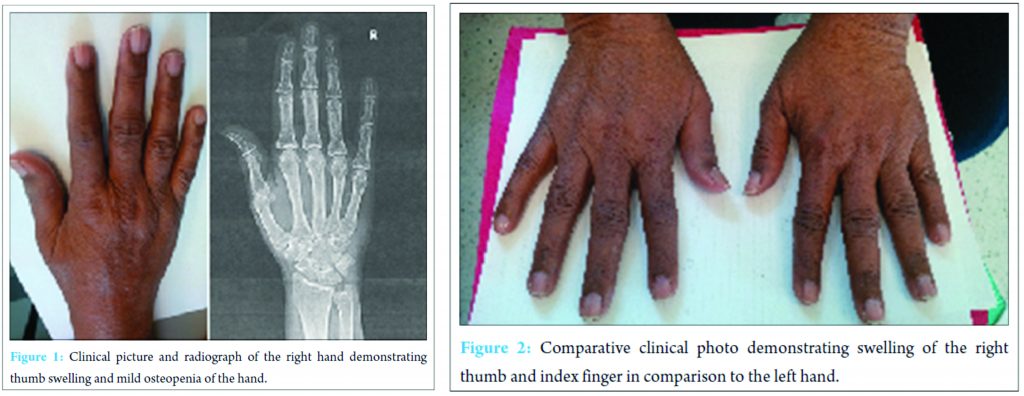

A 71-year-old female presented as a new patient with a chief complaint of right thumb pain that had been present for 2 months before presentation. The patient reported that the onset of her pain began after an episode of shingles involving her right shoulder and her right hand. Since the shingles episode, the patient noted significant pain over the dorsum of the interphalangeal joint of the right thumb. On physical examination, she was found to have discoloration of the right thumb with decreased range of motion of the interphalangeal joint. There was no appreciable swelling. X-rays of her right hand were normal. Her limited range of motion was initially thought to be stiffness as a consequence of guarding the painful hand for an extended period. Consequently, she was prescribed 4 weeks of physical therapy for range of motion exercises. At her 1-month follow-up visit, she stated that the physical therapy slightly helped her range of motion but was not helpful in decreasing her right thumb pain. The right-hand exam demonstrated a decreased range of motion with mild diffuse swelling of the index finger and thumb. There was pain with range of motion of the interphalangeal joint of the thumb as well as hypersensitivity and allodynia over the dorsal ulnar aspect of this region. The patient was diagnosed with CRPS of the right-hand status post shingles of the right upper extremity. She was prescribed vitamin C 500 mg daily for 15 days and gabapentin at a dose of 300 mg 3 times per day. She was also advised to continue physical therapy for the range of motion and desensitization treatment. The patient was seen for follow-up 1 month later with only slight improvement of her pain despite our interventions and complained of periodic swelling of the right index finger and thumb. Her exam was unchanged and her right-hand X-ray demonstrated mild diffuse osteopenia (Fig. 1). She was instructed to continue the gabapentin and resume range of motion exercises at home, as she was financially unable to continue physical therapy.

Our case presentation brings forth the question of whether the patient suffered CRPS triggered by the shingles outbreak or if this was simply a case of post-herpetic neuralgia with CRPS-like symptoms. A prospective randomized study by Berry et al. demonstrated that CRPS-like symptoms were found exclusively in patients whose herpetic rash extended into the affected extremity. Further, that study found that the more distal the herpetic rash on an extremity, the more severe and the longer the clinical course. In that series of 25 patients, no subject progressed to severe CRPS with the associated symptoms of sweating, hair and nail changes, severe dystonia or joint deformity [2]. In our patient, we noted similar signs and symptoms of pain, asymmetrical skin discoloration, edema, and decreased range of motion to the thumb and index finger. However, at no time did the patient demonstrate increased perspiration, hair and/or nail changes or joint deformity to the hand (Fig. 1 and 2) that could be associated with CRPS. This case also highlights the difficulty in making the clinical diagnosis. Other common conditions, such as rheumatoid arthritis and osteoarthritis, may also present with hand pain associated with decreased range of motion. In this case, we used the Budapest criteria to make the clinical diagnosis of CRPS (Table 1) [3]. The diagnosis may have been missed if not for using the diagnostic criteria. A delay in diagnosis would have led to a delay in treatment with possibly an even longer course of recovery for the patient. Our primary modality of treatment planned for this patient was to be an extended physical therapy regimen. There is evidence to suggest that this modality is helpful in decreasing the symptoms of CRPS [4, 5]. Physical therapy using graded motor imagery for an extended period up to 1 year may be required [4]. Our patient had a barrier to extended physical therapy due to insurance limitations. This is an ever increasing issue, and patients, as well as physicians, may need to work with third-party payers to extend access to physical therapy longer than a few visits over a few weeks.